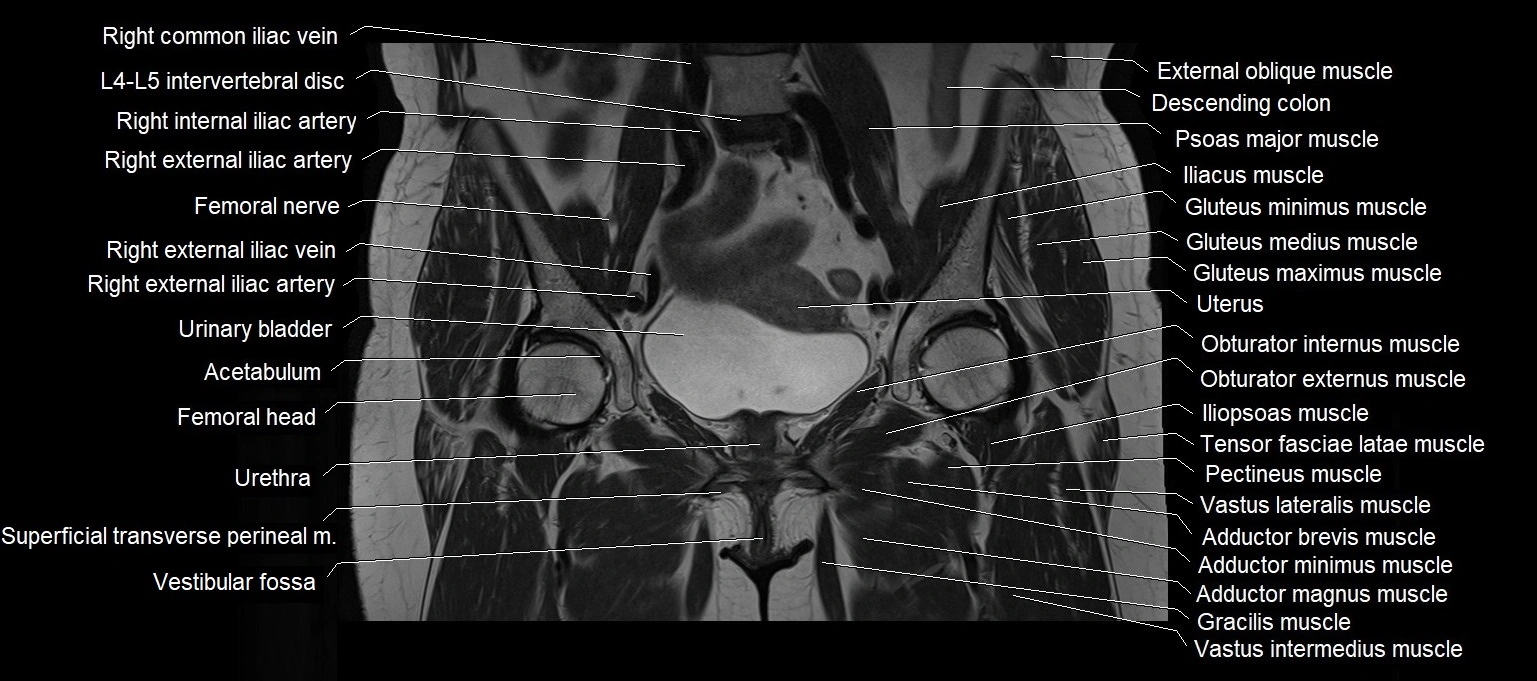

- Acetabulum

- Adductor brevis muscle

- Adductor magnus muscle

- Adductor minimus muscle

- Femoral nerve

- Iliopsoas muscle

- Levator ani muscle

- Obturator externus muscle

- Obturator internus muscle

- Pectineus muscle

- Psoas major muscle

- Quadratus femoris muscle

- Superficial transverse perineal muscle

- Tensor fasciae latae muscle

- Urinary bladder

- Uterus

- Vastus intermedius muscle

- Vastus lateralis muscle

- Vestibular fossa